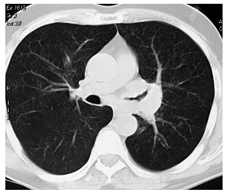

Органы грудной клетки (средостение, легкие,

плевра)

Рентгеносемиотика заболеваний этих органов

полностью совпадает с базовой рентгенодиагностикой при большей информативности

КТ (те же признаки улавливаются более детально). Более точные сведения можно

получить о прорастании новообразования из легкого в плевру или средостение, из

плевры - в мягкие ткани и костный каркас грудной стенки, в грудные позвонки, из

средостения - в обратном направлении. Кисты и опухоли данных органов

визуализируются четко. При КТ видны даже неизмененные медиастинальные

лимфатические узлы. Пораженные лимфатические узлы могут быть охарактеризованы

по форме, размерам, плотности, склонности к конгломерации и агрессии по

отношению к окружающим тканям. При этом затруднена дифференциальная диагностика

гиперпластической и метастатической лимфоаденопатии, отдельных видов

лимфопролиферативных заболеваний. Невозможна диагностика микрометастазов в

лимфатических узлах. Для оценки состояния лимфатических узлов корней легких

лучше использовать линейную томографию. При установленном диагнозе рака

пищевода КТ применяется для оценки степени распространения экзоорганного

компонента опухоли в средостение. Для диагностики опухолей диафрагмы требуется

применение дополнительных приемов (искусственный пневмоперитонеум). Кисты и

опухоли перикарда доступны для КТ-диагностики, новообразования миокарда могут

диагностироваться этим методом в условиях КТ-ангиографии (приоритет сохраняется

за УЗИ и МРТ)